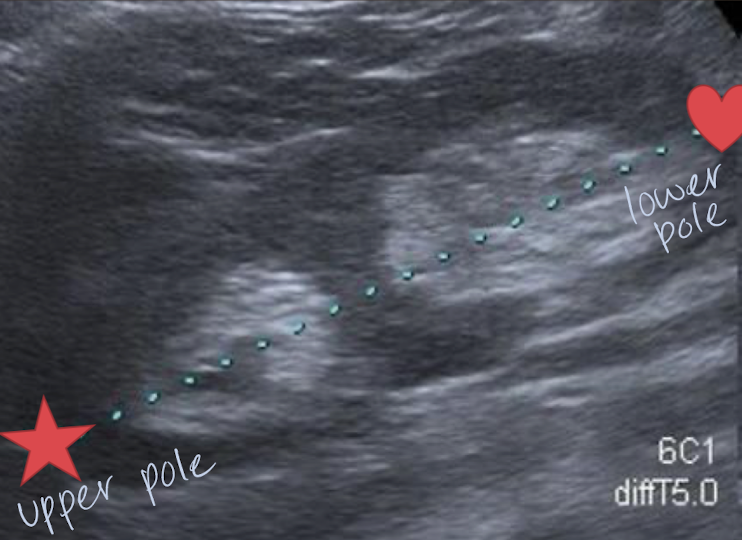

horseshoe kidney

fusion of lower poles, connected via isthmus (anterior to spine and AO)

??